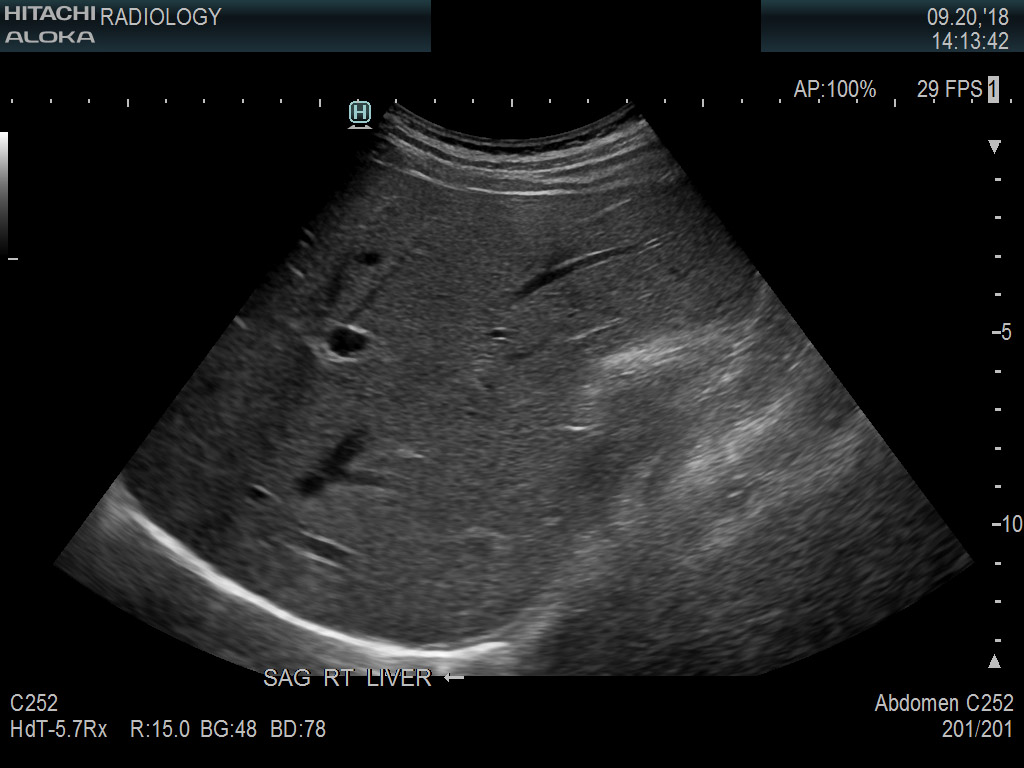

Superior guidance for all applications

Fujifilm Healthcare Americas is committed to designing tools that help surgeons navigate inside the human body and provide the necessary information to immediately make critical surgical decisions.

Fujifilm Healthcare's dedication to Surgeons provides outstanding ultrasound technology, professional support and the specialized tools necessary to best perform comprehensive real-time ultrasound imaging in Breast Surgery, General Surgery, Laparoscopic Surgery, Neurosurgery, Robotic Surgery and Surgical Oncology.

Arietta 70

Recognized for our outstanding image quality, outstanding system reliability and intuitive use of cutting edge technology, Fujifilm Healthcare remains the standard in the field of Surgery.